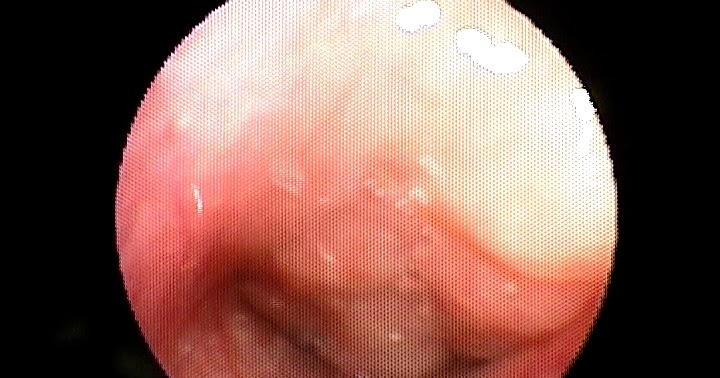

Bazı çocuklarda, sık hastalık geçirmeye bağlı olarak ya da genetik yapılarından kaynaklı olarak geniz eti büyüyebilmektedir. Geniz eti büyümesi nedenleri geniz etleri genellikle yukarıda yazdığım gibi hayatın ilk 6 yaşında büyüme eğilimindedir. Geniz boşluğunda üst kısımda yer alan bir dokuya geniz eti denir.

Geniz eti (adenoidler) vücudu virüslerden ve bakterilerden korumaya yardımcı olurken, bazen şişer ve büyür veya kronik olarak enfekte olurlar. Geniz boşluğunda üst kısımda yer alan bir dokuya geniz eti denir. • çocuğun sıklıkla üst solunum yolu enfeksiyonu geçirmesi, sürekli nezle olması, bademciklerinin devamlı hastalanması ya da alerjik bünyesinin olması.